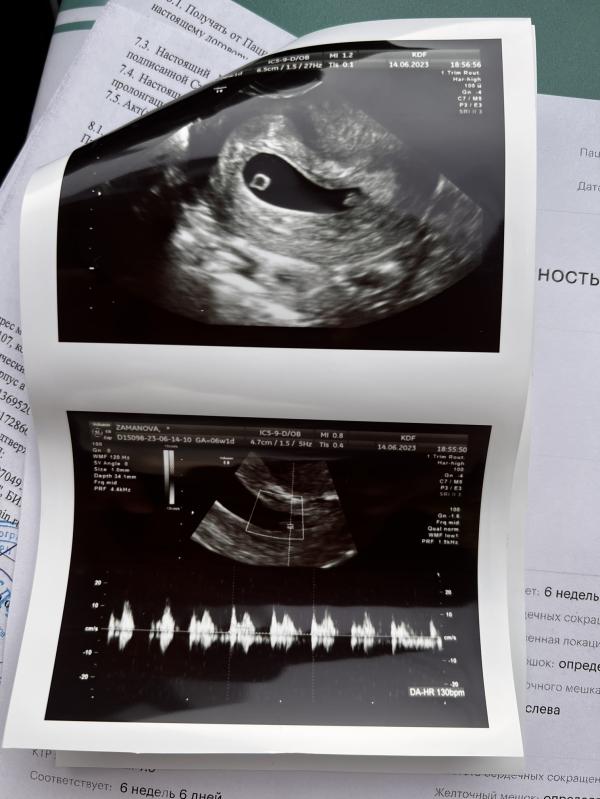

Девочки вот узи кто просил в прошлом посте. Подтвердили что это БЛИЗНЕЦЫ 😍

Перегородки между ними нет. И они копия друг друга, сказала им будет тесно 😅 в одном яйце.